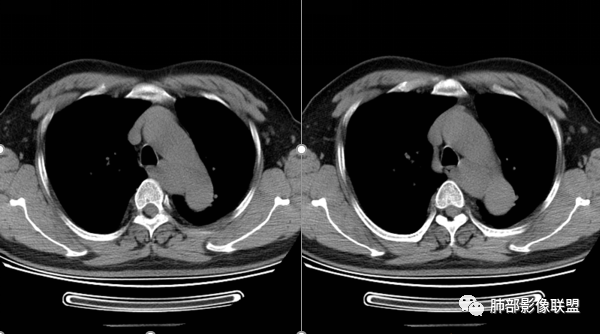

神经源性肿瘤:神经鞘瘤往往有包膜,有张力,典型的形态往往呈类圆形、“逗点形”或“哑铃型”横向延入某一椎间孔内;神经节细胞瘤虽然可以比较柔软,但是具有大量粘液基质,动静脉期强化不明显,延迟期由于粘液对造影剂的滞留,会出现渗透式轻度强化;神经源性肿瘤的解剖位置及形态很重要—沿神经干方向生长走行。后纵隔内神经鞘瘤最常见的是神经根出入椎间孔处,并可沿着肋间神经方向分布,所以后纵膈神经鞘瘤通常横径大,上下径小;神经节细胞瘤可沿着椎旁上下方向分布,所以表现为上下径相对长。